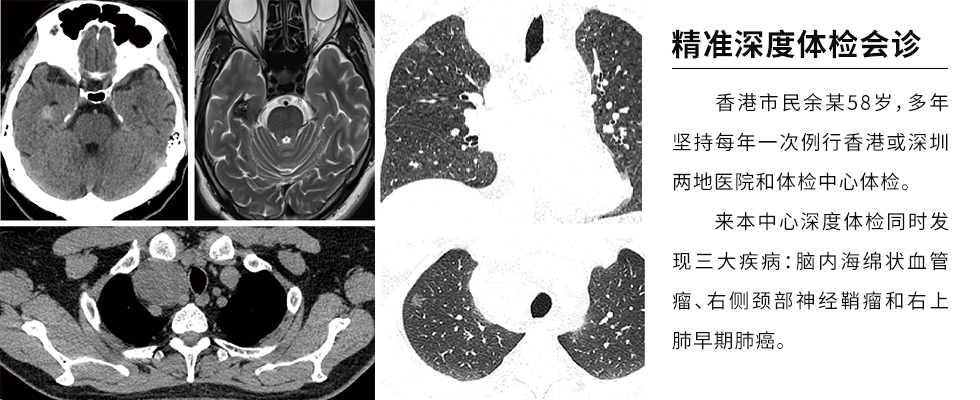

See the film diagnosis for you